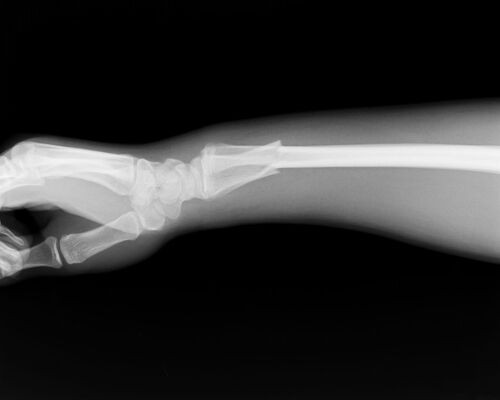

• 骨折レントゲン2

大泉町の接骨院と橈骨遠位端骨折その2

2022/06/01

群馬県邑楽郡大泉町の『けやき接骨院』です。前回の続きです。今日の写真は前回と同じかたですが、写真を撮っている角度(写真と撮っている方向)が違います。ちなみに、見てもらえばわかるかもしれませ...

• 骨折レントゲン1

大泉町の接骨院と橈骨遠位端骨折

2022/05/31

群馬県邑楽郡大泉町の『けやき接骨院』です。過去のものですが、いつかこのブログで書いてみたいと、思っていました。ブログのタイトルにもあるように、今日は、「橈骨遠位端骨折」について書いていき...